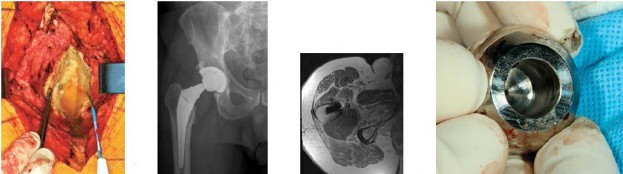

show the intraoperative photograph, anteroposterior radiograph, and axial MRI scan of a 63-year-old man who had right groin pain 18 months after undergoing an uncemented right total hip replacement using a modular femoral neck implant and a metal-on-polyethylene bearing. His laboratory studies revealed an erythrocyte sedimentation rate of 8 mm/h (reference range, 0-20 mm/h) and C-reactive protein level of 5.4 mg/L (reference range, 0.08-3.1 mg/L). A preoperative aspiration revealed cultures that were negative for infection. A cell could not be obtained for evaluation because the cells were “degenerative.” At the time of surgery the joint fluid was turbid in appearance; the periarticular tissues appeared avascular and tan/beige in color. An intraoperative frozen section was negative for acute inflammation.

The implants were solidly fixed to bone. The cause of this patient’s symptoms and the intraoperative findings most likely are attributable to

Metal debris has caused an adverse local soft-tissue response in this scenario. The laboratory studies are all negative for infection. The MRI scan shows a large soft-tissue mass that is posterior to the hip and originating from the hip joint. The dysvascular appearance of the tissues is typical for an adverse tissue response to metal. Even though the bearing is polyethylene, the modular junctions created sufficient metal debris to cause the reaction. Figures 60d and 60e show metal debris inside of the removed femoral head and corrosion of the modular neck. The other diagnoses are not consistent with this clinical presentation. PREFERRED RESPONSE: 2